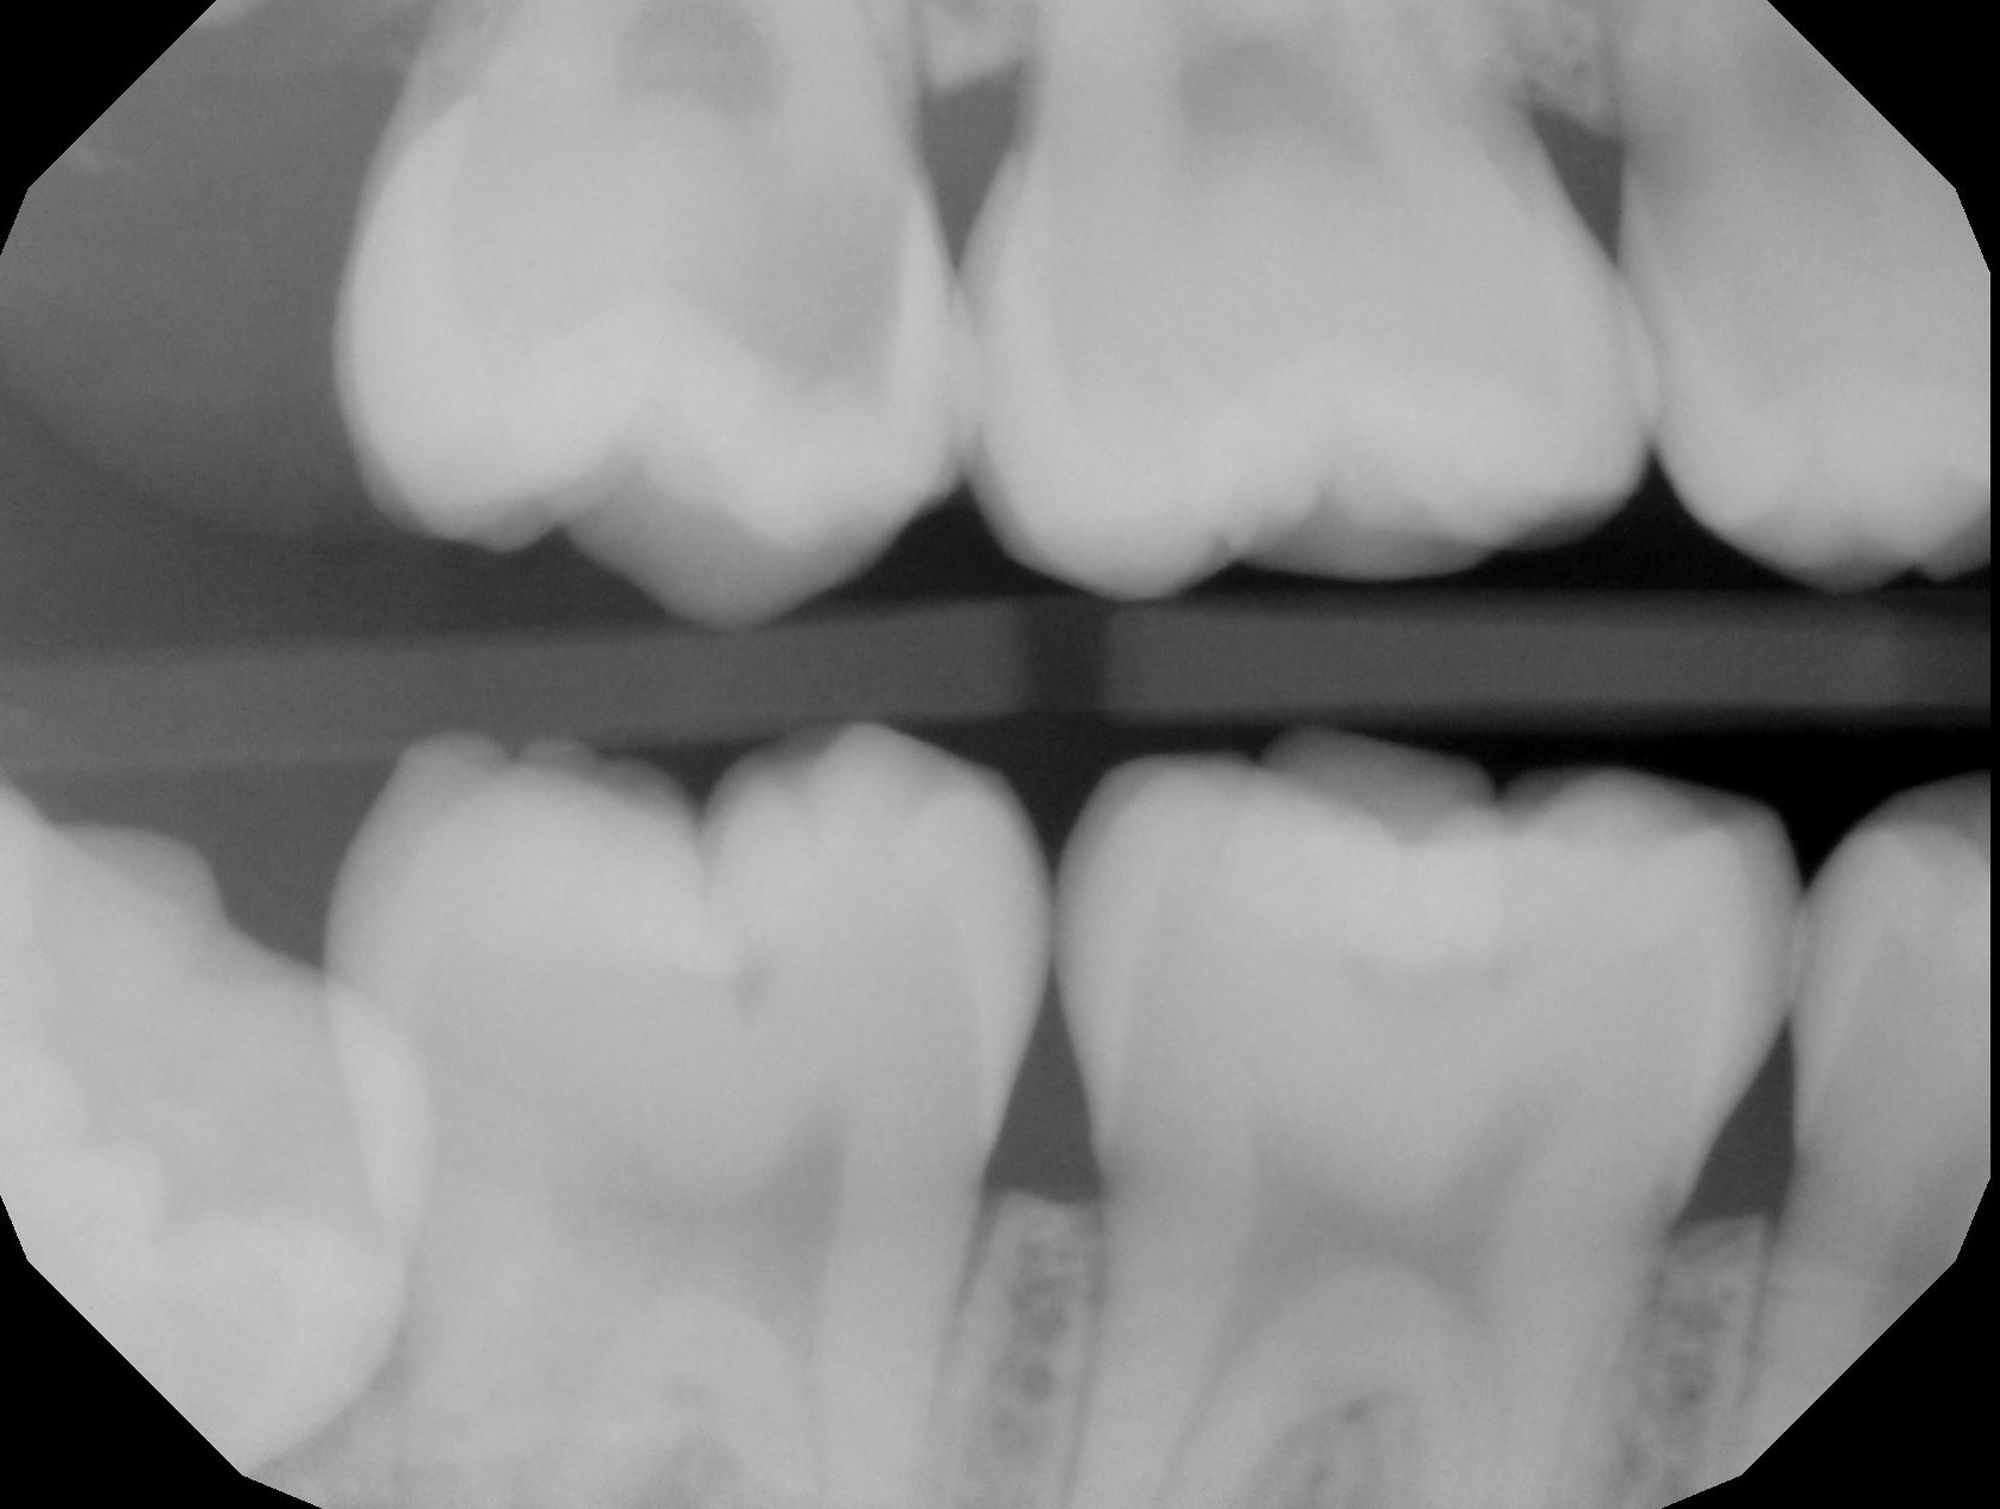

Figure 2A

Figure 2B. Deep caries associated with signs and symptoms of reversible pulpitis in tooth No. 29 (A) resulted in hyperemic pulp tissue extending throughout the pulp chamber, warranting bioceramic pulpotomy to achieve hemostasis (B).